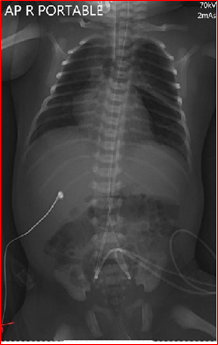

The x-ray (Figure 1) confirmed the position of the both lines at thoracic vertebra 7 levels (T 7) for the UAC and thoracic vertebra 10 level (T10) for the presumed UVC. The X- ray included the chest only and hence the whole courses of both catheters were not identifiable. However, they both looked heading toward the left side of the vertebrae. Dextrose 10% was infused through the lower central line which is presumed to be UVC, while antibiotics were given through peripheral venous line as per the neonatal unit policy.

Figure 1 (First X-ray: Two vascular catheters were identified with the tips positioned at level T7 and T10 thoracic Vertebrae, The view did not include full course of the catheters).